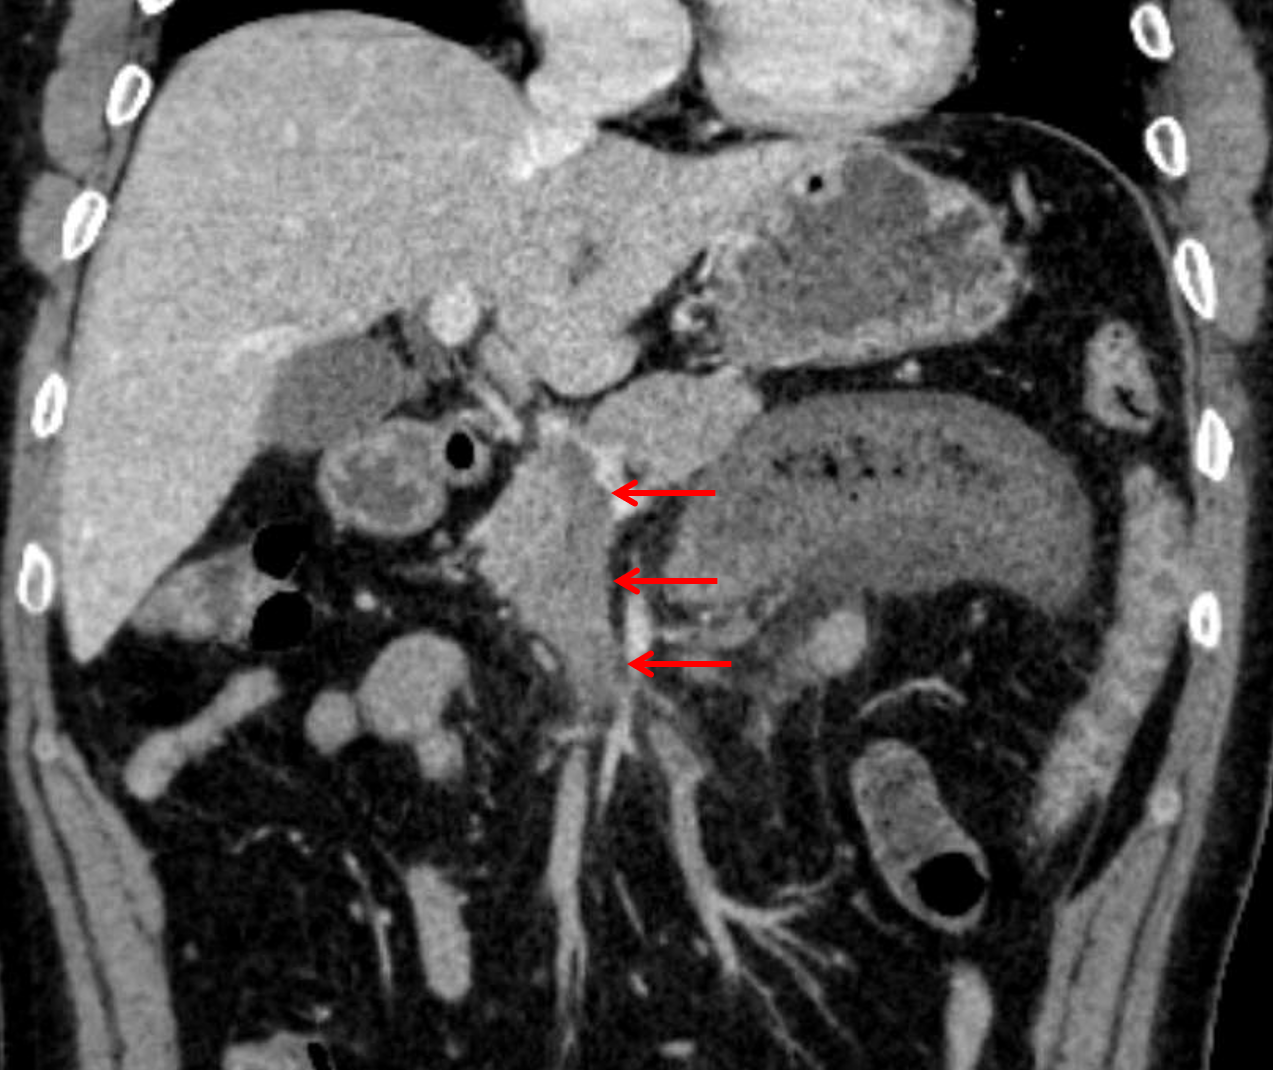

Sample ReportFindings concerning for developing segmental ischemia involving the proximal jejunum secondary to SMV thrombosis. Nonocclusive thrombus also extends slightly into the main portal vein. No pneumatosis, portal venous gas, or pneumoperitoneum.